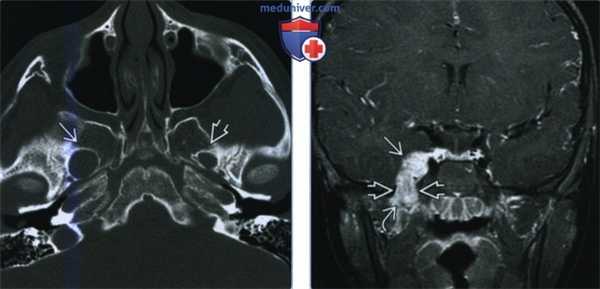

(Слева) МРТ Т2ВИ FS, аксиальная проекция. Наблюдается повышенная интенсивность сигнала крыловидных мышц и глубокой части височной мышцы. Затемнение ячеек сосцевидного отростка говорит о дисфункции слуховой трубы вследствие паралича мышцы, напрягающей небную занавеску. У этого пациента была обнаружена менингиома, локализующаяся в тройничной полости (здесь не отображена).

(Справа) МРТ Т1ВИ FS с КУ, коронарная проекция, этот же пациент: умеренное накопление контраста в крыловидных мышцах и уменьшение в размерах трубного валика. Такие находки говорят о подострой денервационной атрофии нижнечелюстного нерва. (Слева) МРТ Т1ВИ, коронарная проекция. Хроническая жировая атрофия левой височной и жевательной мышц? которая говорит о хроническом повреждении нижнечелюстного нерва. По сравнению со здоровой стороной левая челюстно-подъязычная мышца также уменьшена в размерах, имеется незначительная жировая инфильтрация.

(Справа) МРТ Т1ВИ в аксиальной проекции, этот же пациент. Правая челюстно-подъязычная мышца и подкожная мышца шеи интактны. Их отсутствие/сильная атрофия слева говорят, что повреждены и нижнечелюстной (челюстно-подъязычная мышца), и лицевой (подкожная мышца шеи) нервы.

(Слева) МРТ Т1ВИ в коронарной проекции. Справа переднее брюшко двубрюшной мышцы и подкожная мышца шеи интактны. Слева челюстно-подъязычная мышца и подкожная мышца шеи визуализируются плохо, что является следствием хронического повреждения нижнечелюстною и лицевою нервов, соответственно.

(Справа) МРТ Т1ВИ в аксиальной проекции, тот же пациент. Справа переднее брюшко двубрюшной мышцы и подкожная мышца шеи интактны. Слева обе мышцы подверглись жировой атрофии и из-за этого не видны. У пациента была обнаружена опухоль основания черепа, затрагивающая овальное отверстие и коленчатую ямку.

(Слева) МРТ Т1ВИ FS с КУ, коронарная проекция. Аденокистозная карцинома, которая распространяется в полость черепа через овальное отверстие. Подострая денервация жевательной мышцы сопровождается накоплением в ней контрастного вещества.

(Справа) МРТ Т1ВИ FS в аксиальной проекции, тот же пациент. Накопление контраста в жевательной и латеральной крыловидной мышцах, характерное для подострой денервации. Объем мышечной ткани начинает снижаться, что говорит о том, что подострая стадия подходит к концу.

(Слева) МРТ Т2ВИ FS, аксиальная проекция. На Т2 сигнал гиперинтенсивный, крыловидные и височная мышцы отечны, что говорит об острой-подострой стадии денервации. На этом срезе нижнечелюстной нерв выглядит как структура пониженной интенсивности, располагающаяся в жевательном пространстве.

(Справа) МРТ Т1ВИ с КУ в аксиальной проекции, тот же пациент. Причиной денервации является менингиома, расположенная в области пещеристою синуса и предмостовой цистерны. Шваннома тройничного нерва выглядит аналогично.